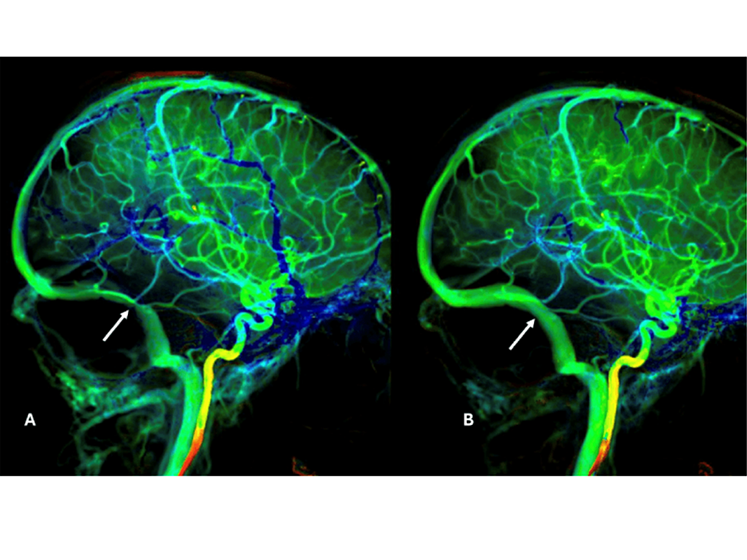

Minimally Invasive Treatment for Idiopathic Intracranial Hypertension

Srikanth Reddy Boddu, MD, an interventional neuroradiologist at NewYork‑Presbyterian and Weill Cornell Medicine and director of interventional neuroradiology at NewYork‑Presbyterian Queens, is one of a few physicians in the country who treats idiopathic intracranial hypertension (IIH) with minimally invasive techniques. Recent research on IIH outlined challenges with the standard of care, pharmacologic treatment, which often comes with side effects, or a ventriculoperitoneal (VP) shunt. Nearly half of VP shunts fail after two years, necessitating additional procedures. Dr. Boddu and his team have innovated a third option for patients: venous sinus stenting. This option is the most effective treatment for IIH according to meta-analyses, offering immediate relief from pulsatile tinnitus and potentially resolving vision issues within three months.